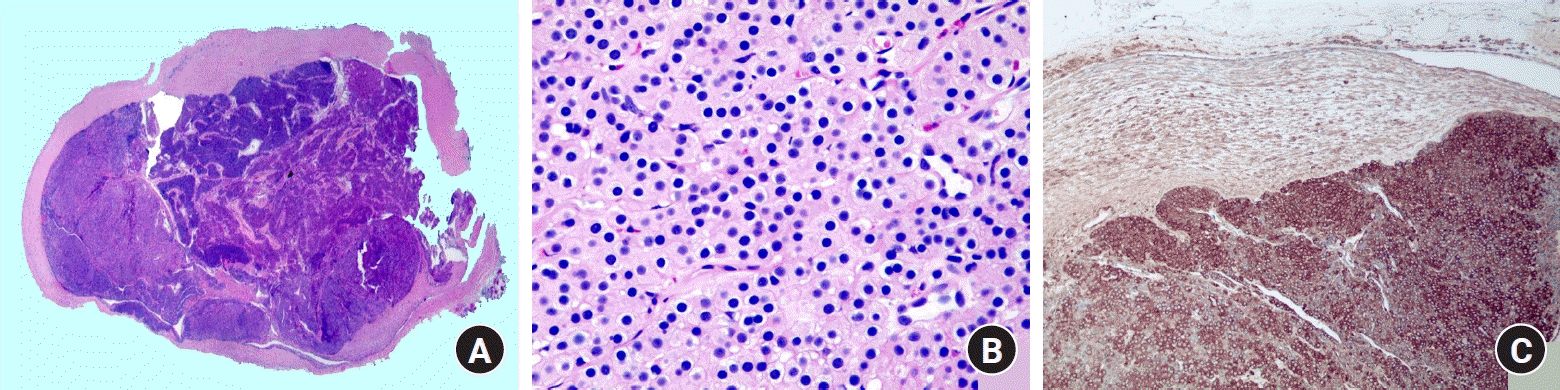

Microscopic examination revealed an encapsulated tumor comprising solid sheets of blue cells, which consisted of round glomus cells with increased vascular spaces (Fig. 3A, 3B). The neoplastic cells were positive for smooth muscle actin immunostaining (Fig. 3C). Sectional views of the tubular structure attached to the tumor revealed the presence of a blood vessel (Fig. 4A, 4B). Notably, a compressed luminal space, positive for the vascular marker CD31, was identified on the tumor’s undersurface (Fig. 4C), indicating a potential connection between the blood vessel of the tumor’s undersurface and the tubular structures (Fig. 1C). These histopathological features suggested that the GT had exerted chronic pressure on the underlying blood vessels, resulting in firm adherence of the vessel to the tumor. Postoperative recovery was uneventful, and the paroxysmal pain resolved immediately following surgery. The patient reported excellent postoperative outcomes at the 3-month follow-up with no observed complications.

Histopathologically, GTs are composed of three components: glomus cells, vasculature, and smooth muscle cells. These tumors may be subcategorized as solid GTs (poor vasculature and scant smooth muscle component), glomangiomas (prominent vascular component), or glomangiomyomas (prominent vascular and smooth muscle components). The most prevalent variant is the solid GT, accounting for 75% of cases, while glomangioma and glomangiomyoma make up 20% and 5% respectively [5]. In our case, the lesion also corresponded to the histopathologic features of a solid GT, including the predominance of glomus cells, poor vasculature, and rare smooth muscle cells.

Fig. 3.

Histopathological features. (A) An encapsulated tumor containing solid sheets of blue cells (H&E stain, ×15). (B) Round to oval glomus tumor cells with slit-like vascular spaces (H&E stain, ×400). (C) Glomus tumor cells positive for smooth muscle actin immunostaining (×100).